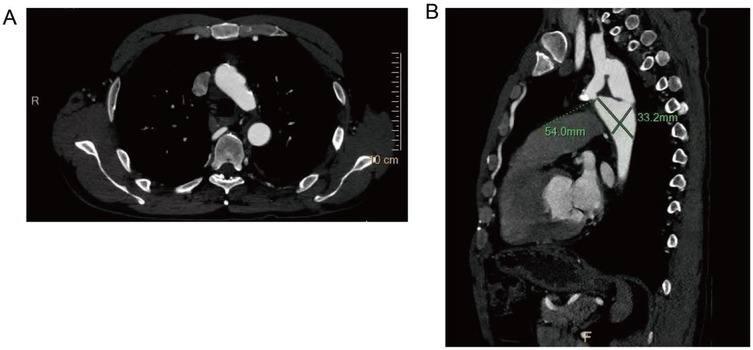

After comprehensive evaluation and multidisciplinary team (MDT) discussion, surgical correction was deemed necessary. Given the patient's age, vascular anatomy, and the extent of aortic interruption with heavy calcification, endovascular intervention was considered unfeasible. An extra-anatomic bypass procedure using a left subclavian artery-to-descending aorta synthetic graft was selected as the optimal approach. The left subclavian artery, with an internal diameter of 15 mm, was suitable as the proximal anastomosis site. A post-stenotic aneurysm of the descending aorta was also noted, measuring approximately 54.0 mm × 33.2 mm in maximal cross-sectional diameter.

Figure 5

Scattered calcified plaques are observed in the walls of the aortic arch and brachiocephalic trunk, with irregular lumens as shown in (A). The descending aorta shows poststenotic aneurysmal dilation, with dimensional measurements provided in (B).